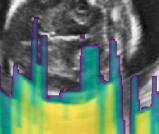

Fig. 6 compares the shadow confidence maps of the state-of-the-art methods and the proposed methods. RW and have the same parameters as used for Table I. The shadow confidence maps of the baseline, the proposed method and the proposedAG method are generated directly from input shadow images by confidence estimation networks. Overall, the proposed method and the proposedAG method achieve more visually reasonable shadow confidence estimation than the baseline and the state-of-the-art on different anatomical structures shown in Fig. 6. The proposed method and the proposedAG method are able to highlight multiple shadow regions while the RW algorithm shows limitations for most cases, especially for disjoint shadow regions.

Row I in Fig. 6 shows a fetal brain image from . The confidence estimation of shadow regions from the baseline, the proposed method and the proposedAG method are similarly accurate since we use fetal brain images to train the confidence estimation networks in these three methods. These outperform [16] and [22]. Rows (II-IV) in Fig. 6 show shadow confidence maps of non-brain anatomy from , including lips, abdominal and cardiac. The baseline failed on unseen data during inference. However, the proposed methods are able to generate accurate shadow confidence maps because of the generalized shadow features obtained by the shadow-seg module. Furthermore, the “Lips” example shows that our method is capable of detecting weaker shadow regions that have not been annotated in manual segmentation. This indicates that the confidence estimation network has learned general properties of shadow regions.